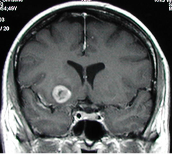

Das begann in den 1970er Jahren mit der Einführung des Operationsmikroskops, das wesentlich schonenderes und weitaus sichereres Vorgehen ermöglichte. Heute kann über spezielle Vorbehandlung und Beleuchtung Tumorgewebe sichtbar gemacht und es können die Strömungsverhältnisse in Blutgefäßen des Gehirns dargestellt werden.